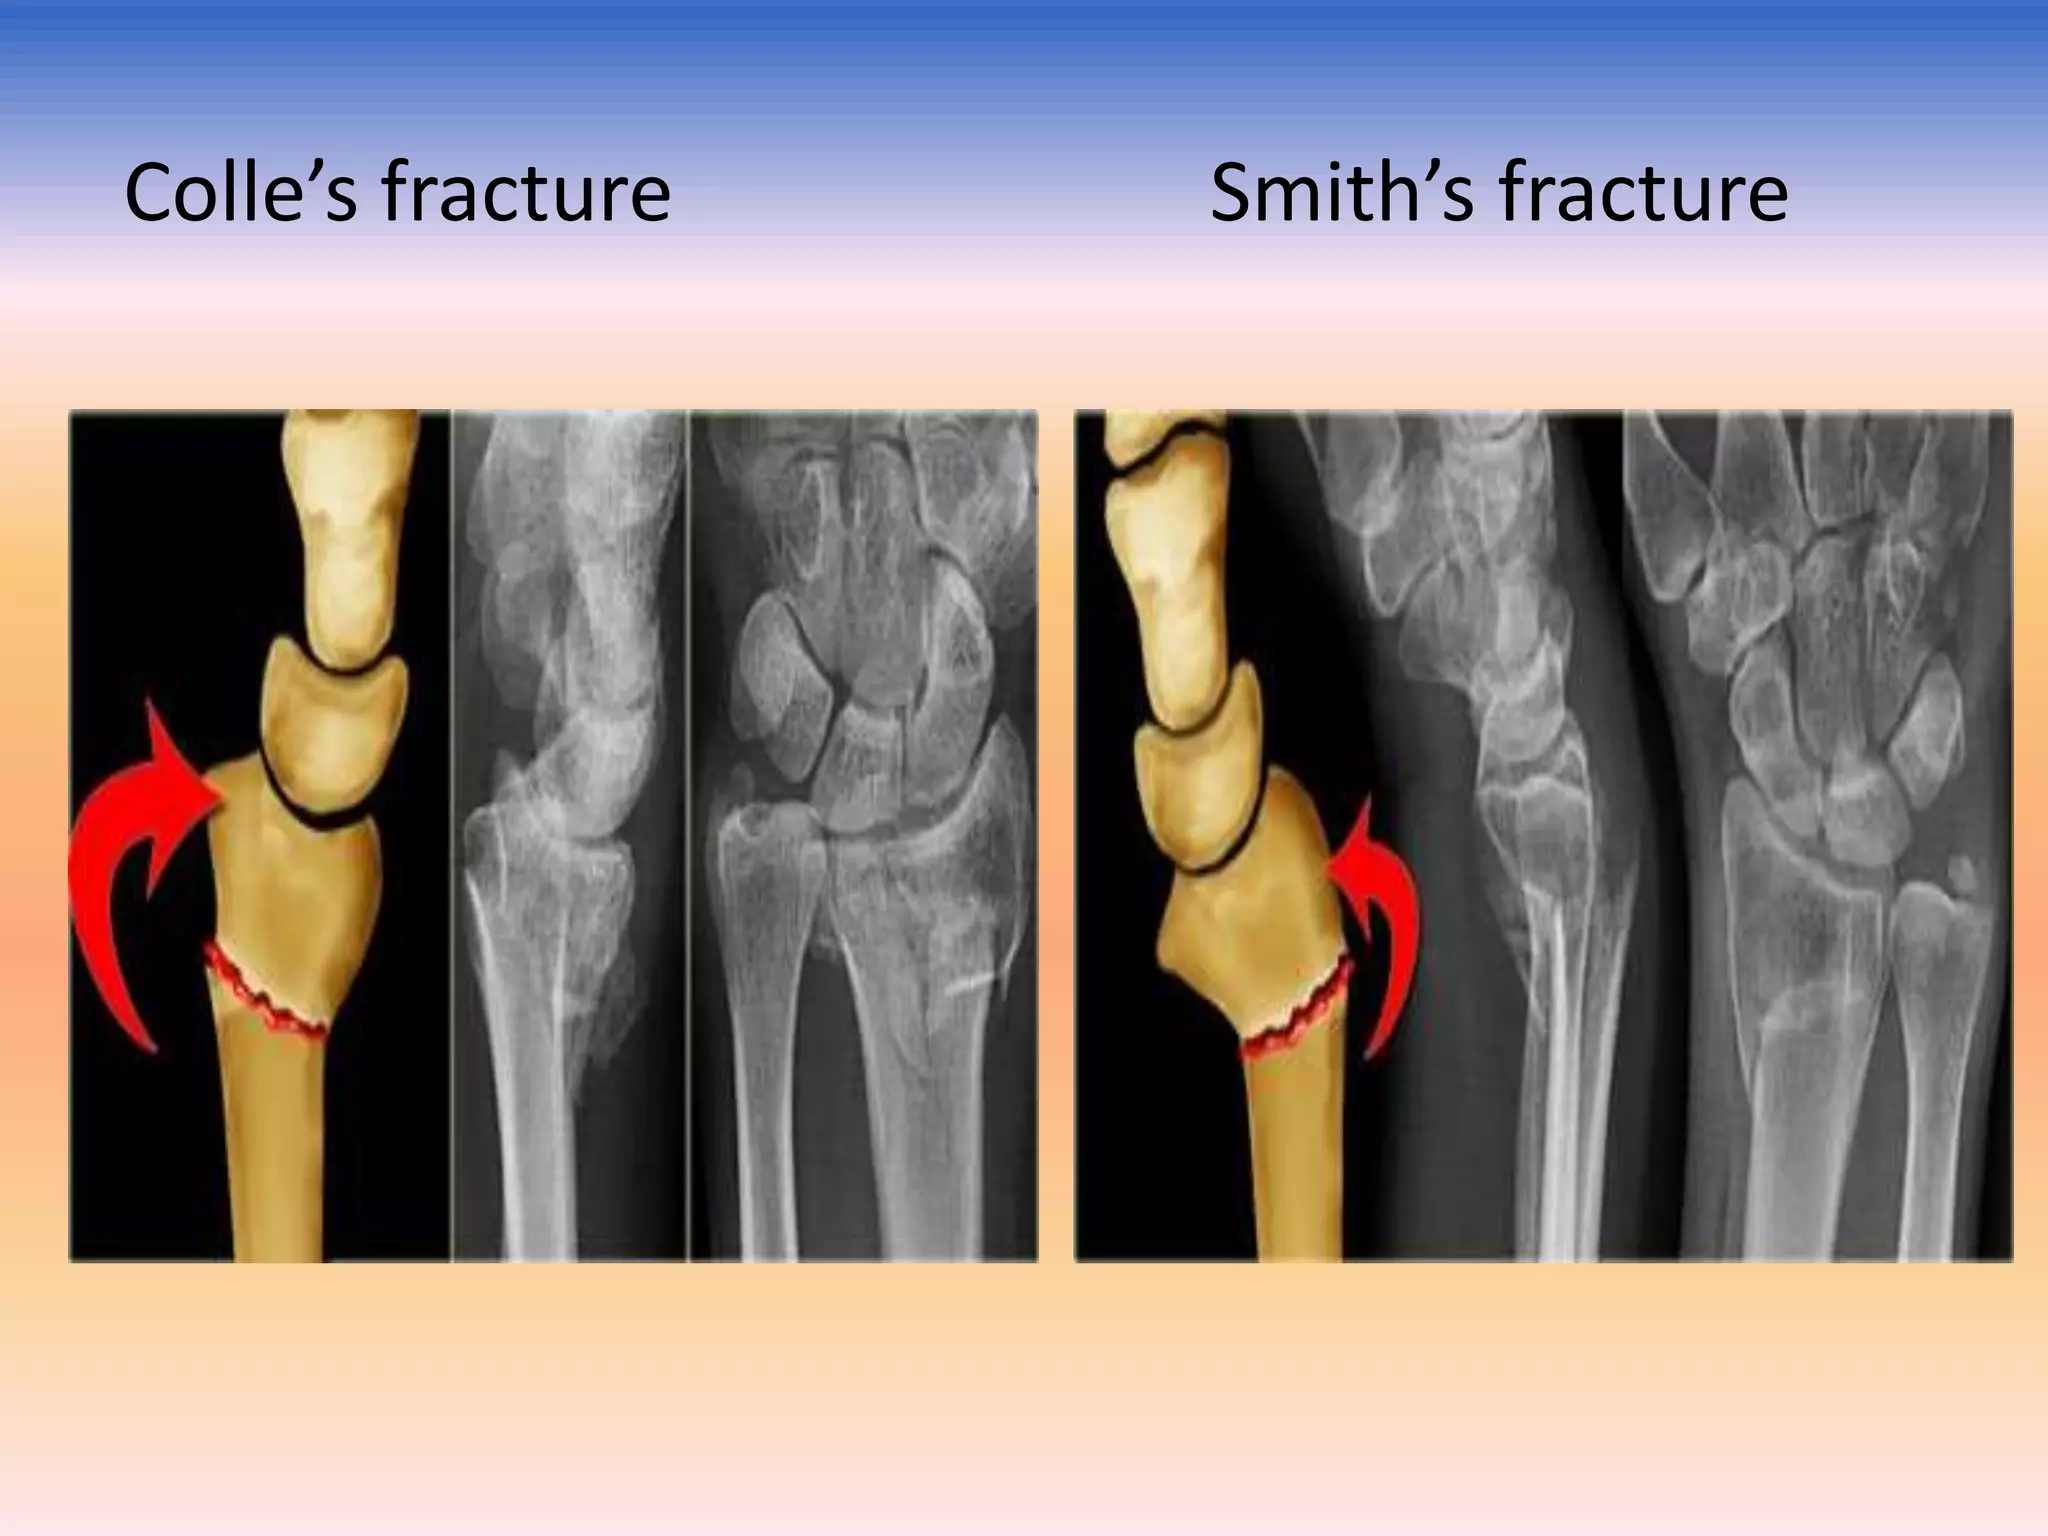

Colle`s and smith`s fracture

Describe by : - Abraham Colle's - 1814.

It is not just fracture lower end of radius but

a fracture dislocation of the inferior

radioulnar joint .

Occurs about 2.5 cm above the carpal

extremity of the radius .

A Smith's fracture, also sometimes known

as a reverse Colles' fracture is a fracture of

the distal radius. It is caused by a direct

blow to the dorsal forearm or falling onto

flexed wrists, as opposed to a Colles'

fracture which occurs as a result of falling

onto wrists in extension.

Colle’s fracture

Smith’s fracture